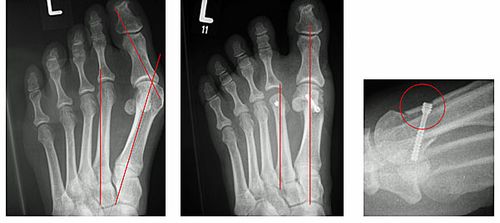

Abb.2: Korrektur einer leichten Hallux valgus Fehlstellung durch eine Chevron Osteotomie (Distale Metatarsale I Osteotomie) mit versenkter Schraube. Der Vorfuß wurde verschmälert und die Knochenachsen begradigt.

Abb.3: a Korrektur einer mittelschweren Hallux valgus Fehlstellung durch eine Basisosteotomie.

b Korrektur einer schweren Hallux valgus Fehlstellung mit luxierten Krallenzehen und chronischer Metatarsalgie durch eine Lapidus Arthrodese. Mit dieser Technik können selbst hochgradige Fehlstellungen begradigt werden. Bei beiden Techniken wird der Knochen wird mit einer winkelstabilen Platte fixiert. Dies bietet ein höchstes Maß an Stabilität und ermöglicht die sofortige postoperative Belastung.